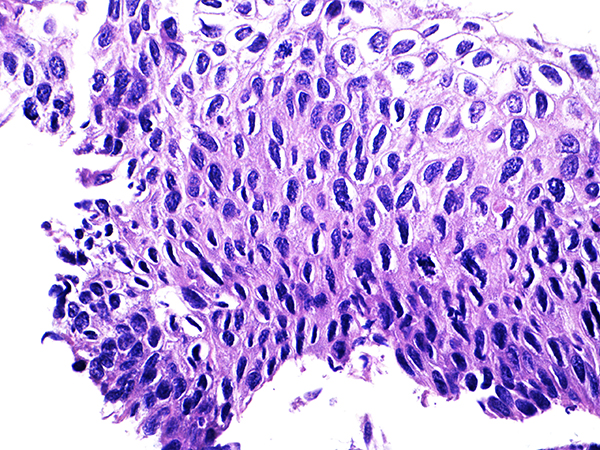

![]() Case 2

Soft Bx CIN 2 10x - Low Power |

Soft Bx CIN 2

40x - High Power